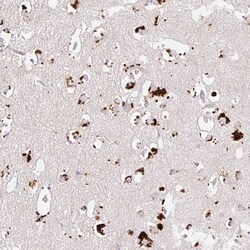

- Immunohistochemical analysis of CLEC3A in human cerebral cortex using CLEC3A Polyclonal Antibody (Product # PA5-62424) shows strong granular pattern cytoplasmic positivity in neuronal cells.